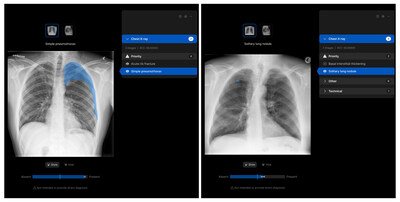

The solution is deployed within the radiology department, where it will assist radiologists by triaging studies, identifying and localising findings, and generating AI-assisted draft reports. These draft reports are reviewed and validated by radiologists prior to sign-off, ensuring full clinical oversight and control.

“We are proud to partner with Manipal Hospitals on the deployment of Harrison’s CXR solution in India,” said Dr Aengus Tran, CEO of Harrison.ai. “The solution which can detect and localise close to 125 findings helps clinicians ensure accuracy of diagnosis. This collaboration reflects a shared vision to responsibly apply AI in healthcare, supporting clinicians, improving efficiency, and ultimately enhancing patient care and experience.”